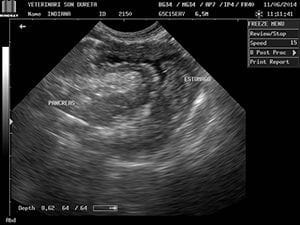

Rápidamente lo trajeron al Servicio Veterinario de Urgencias de la Clínica Veterinaria Son Dureta. Pancho llegó con un shock hipovolémico, (falta de oxígeno en órganos y tejidos debido a la pérdida tan grande y aguda de líquidos y sangre) sus mucosas estaban muy pálidas, su pulso era débil y su temperatura corporal muy baja. Se realizaron analíticas, donde no se identificaron órganos internos dañados aunque las enzimas hepáticas estaban alteradas y por supuesto, las alteraciones del sistema digestivo asociadas a su estado.